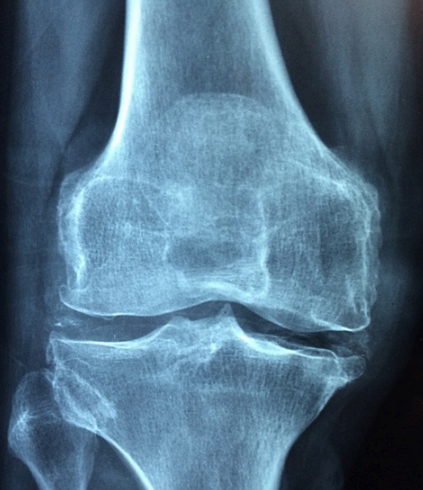

위에 사진은 콘드로이친 1200mg 인체적용 시험결과 사진으로 관절사이 평균 너비 유지 확인, 관절 통증평가 점수(VAS) 유의적 개선 확인, 양쪽 무릎에 대한 관절 통증 및 기능평가 점수 유의적 개선 확인에 대한 인체적용 시험결과입니다.